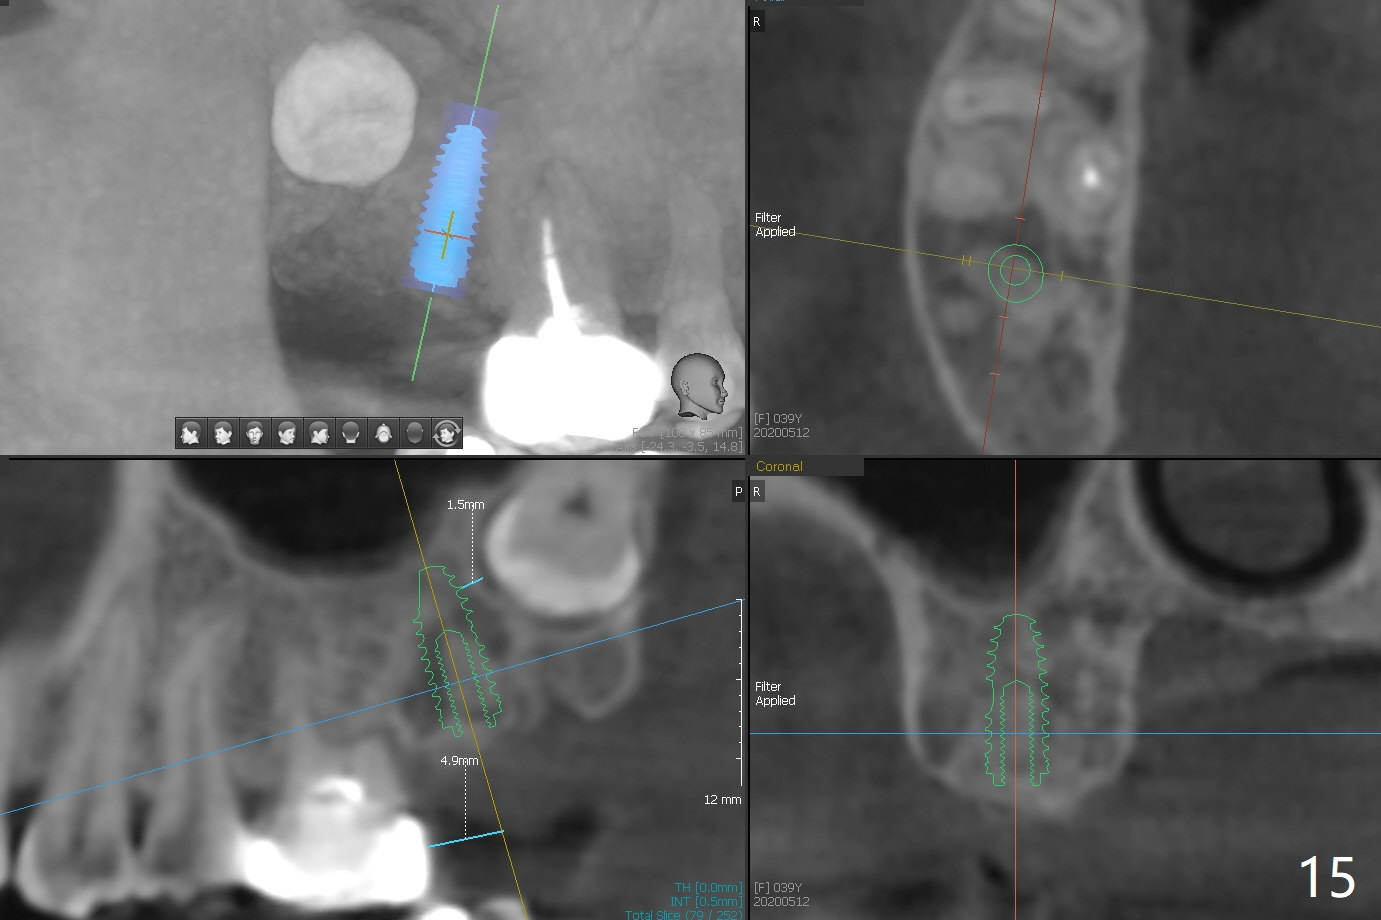

The socket of #2 heals 13 days postop; it appears that the bone graft remains in place (Fig.7,8 *). The patient is instructed to return in 3-4 months for impression and CT for guide. The socket heals 4 months postop (Fig.9,10). She plans to have implant next year, since she wants to add another insurance. The patient returns for implant without removal of the third molar 2 years 4 months post socket preservation (Fig.11). A 5x7.3 mm implant can be placed without invading the sac of the impacted third molar (Fig.12). In fact the lab has a better plan. A lump of bone forms in the previous socket 1 year 4 months postop (Fig.13 *). The ridge is wide and dense (Fig.14). A narrow implant placed oblique could be longer (Fig.15), as compared to a wide, short one (Fig.12).